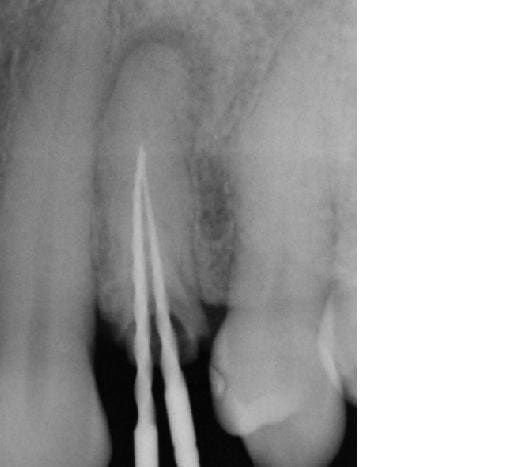

photo lime en place: pas possible aller + loin même en manuel avec une n°8....

1ere endo: lentulo pate trés fluide

2eme: premier tir et relentulo (pate trés fluide poussée par le laser et + épaisse pour la deuxiéme couche au lentulo)

3eme: deuxieme tir (je voulais chopper les 2 racines....) et relentulo et gutta.

ps: cette dent était donnée pour perdue et la seule proposition faite à la patiente était implant.... (idem pour la 22 qui est certes à refaire/reprendre mais sans doute pas perdue....)

y m'a fallu 30 minutes pour desobturer et réobturer, Sc33 sur tenoçns titane et coiffe provisoire posées cet aprtés midi, endo faite y'a 2 jours et RAS.

Algi, si le ciment a pu passer c'est bien qu'une perméabilité existait ? Ou bien est-ce que le laser a permis de virer les calcifications ? As-tu déjà essayé de passer après avoir tiré ?

Bien sur que j'ai essayé de passer, j'ai pas pu mieux faire que les 2 limes en place, sans doute une butée (les calcifications passé le 1/3 coronaire sont trés trés rares et donc à ce stade là c'est en général soit un bouchon soit une butée, les 2 étant iatrogénes).

S'il y une lésion, en règle général, il y a passage. On ne passe pas toujours, mais il existe.

Donc ds ce cas ci(complexe) ou radiographiquement tout semble calcifié, il y a surement une petite butée.

Cela dit, c'est le nettoyage chimique (hypo/edta) qui a permis de dégager le passage. Cela est objectivé radiographiquement par la fusée de ciment. Le laser aurait simplement permis, voire potentialié cette fusée, il me semble...